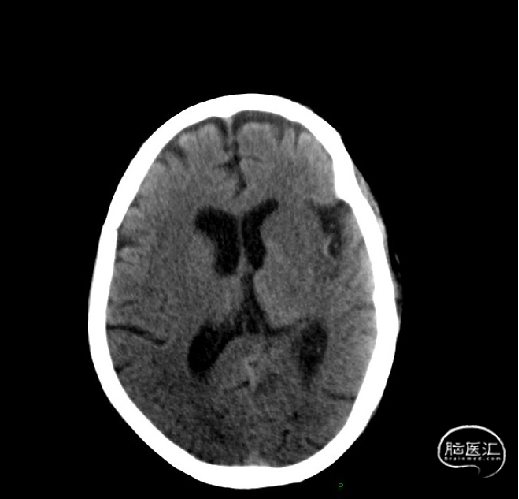

术前CT未见出血。

术前CTA:左侧颈内动脉、椎动脉颅内段、大脑中动脉未见显影,左侧大脑半球远端分支血管较对侧明显稀疏。

CTP:左额叶、基底节存在核心梗死区,体积35.5ml;左大脑半球mismatch体积171.5ml,低灌注体积207ml,比值5.8。